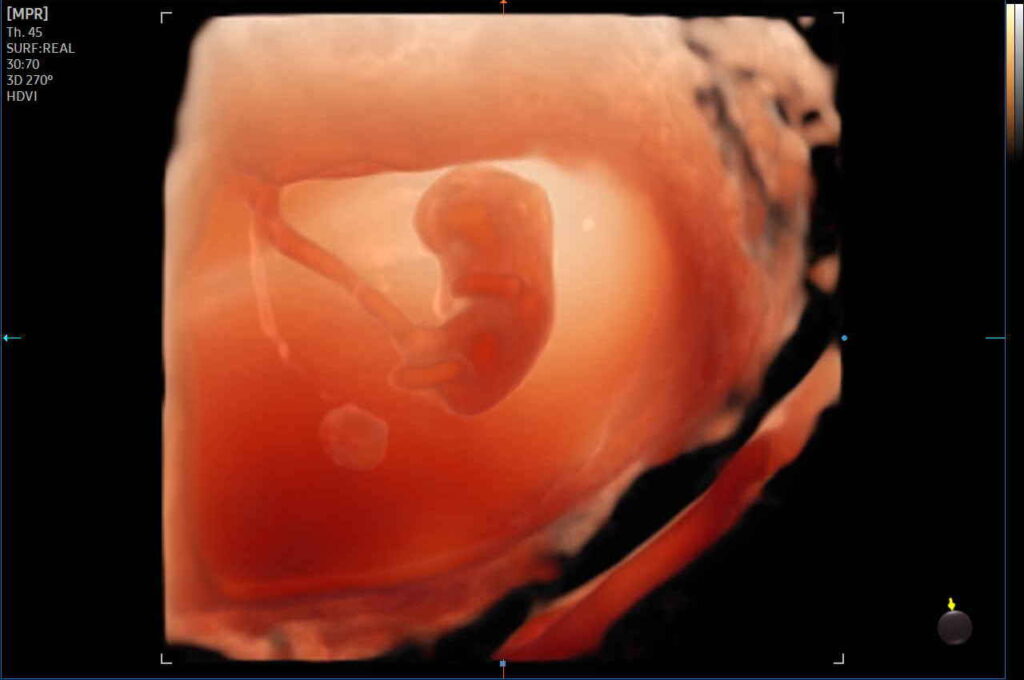

2D pretecho + vroeg kijkje in 3D/4D (10-20 weken)

- Prijs: €65,-

- Duur: 20 minuten

- Inclusief: 2 zwart-wit foto afdrukken en 1 kleurenfoto afdruk

Echo's uit het verleden

Vroeg kijkje in 3D